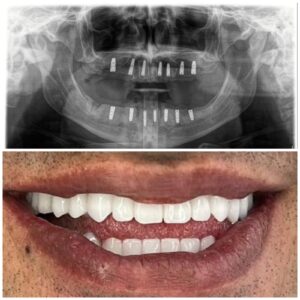

تقنيات حديثة للزراعة

تضيف اجهزه البانوراما الداخلية واجهزة التصوير ثلاثية الأبعاد بعدًا آخر لتقنية الزرع من خلال صورها الدقيقة للفك والأسنان. هذه الدقة ضرورية لتخطيط ووضع الغرسات. يوفر تقييمًا دقيقًا للبنى التشريحيه مثل الأعصاب وجذور الأسنان والجيوب الفكية ومعرفة طبيعة العظم وكثافة وما إلى ذلك ، مما يمنع أي احتمال للفشل الذي يحدث بسبب التشخيص الخاطئ. تم تجهيز مراكز الزرع لدينا بهذه الآلات المتطورة ، مما يمكننا من تنفيذ كل حالة من حالات الزرع بدقه عاليه وأعلى درجات النجاح.